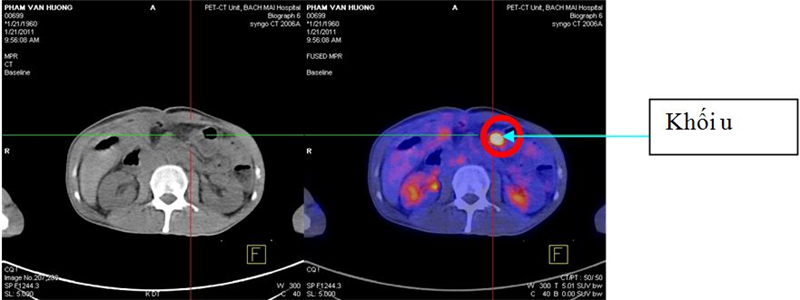

Một số hình ảnh minh họa:

Khối u trực tràng xâm lấn xương cùng, không xác định được mức độ xâm lấn trên hình ảnh CT đơn thuần

Tổn thương u tăng hấp thu F-18 FDG tại đại tràng